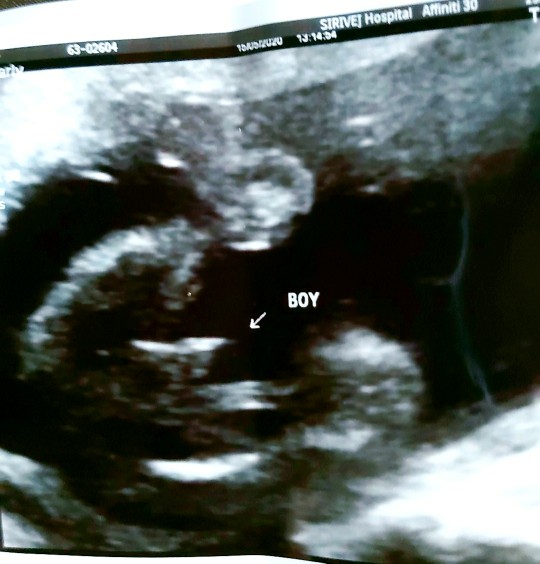

ใบอัลตร้าซาวด์

แม่ๆช่วยดูหน่อยคะ ผช.ใช่ไหมคะ หมอบอก ผช. บ้านไหนได้ ผช. ลงรูปใบซาวด์ให้ดูหน่อยคะ

ชายค่ะ

ผช. ค่ะ

ผ.ช ค่ะ

ผช. จ้า

ผช ค่ะ

ผช.จ้า

ผช.ค่ะ

ผชจ้า

ผช.คะ